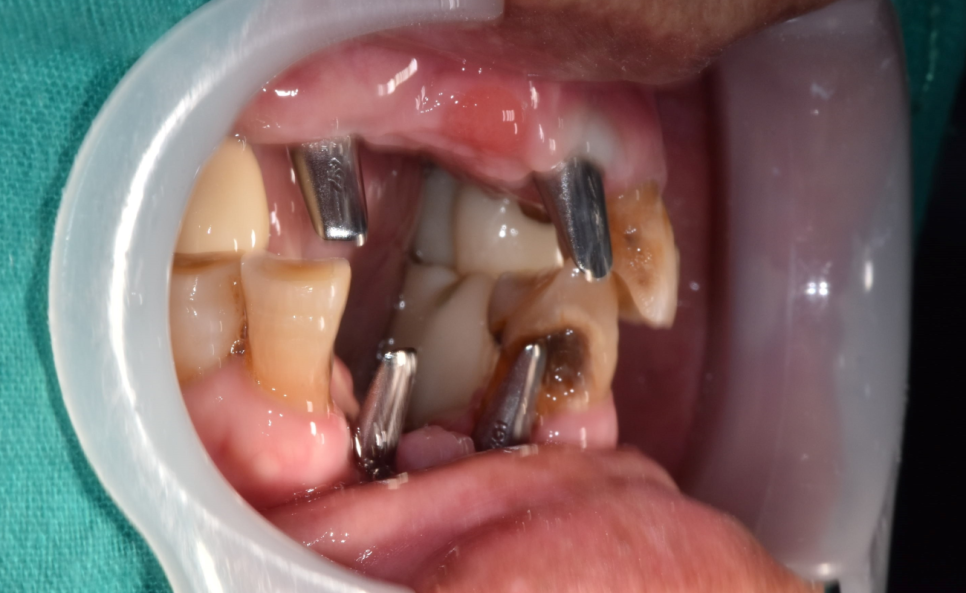

240120

묻어났던 임플란트를 시간이 지나

잇몸 밖으로 꺼내고

뽄을 뜰 준비를 합니다

이 과정을 거치면 천호동 임플란트

80%정도 치료는 끝난겁니다.

240224

잇몸만 아물면

치아 기둥을 만들어 보철을 제작하면 되거든요

240504

기둥을 연결한 모습입니다.